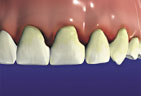

Gum disease is usually caused by plaque, a sticky film of bacteria that constantly forms on teeth. If plaque is not removed with thorough daily brushing and cleaning between teeth, gums become irritated and inflamed. The irritated gum tissue can separate from the teeth and form spaces called pockets. Bacteria move into the pockets where they continue to promote irritation. Left untreated, the process can continue until the bone and other tooth-supporting tissues are destroyed. The early stage of periodontal disease is called gingivitis. It often results in gums that are red and swollen and may bleed easily.

Gingivitis Gingivitis

(bleeding gums)